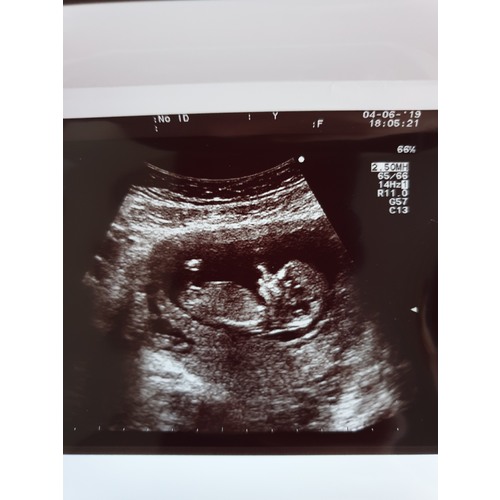

Op 20 mei, met 11+1 een termijn echo gehad. Bij het doorsturen gaf iemand aan het te kunnen zien. Wilde het niet weten van haar maar mn nieuwsgierigheid was toch mega getriggert dus later alsnog aan iemand gevraagd. Die zegt een meisje...

17 juni hebben we een extra echo zelf ingepland (15+1) om te kijken wat het word. Zou het dan echt?! Zo benieuwd!!

De mensen die uiteindelijk mn foto met eventuele nub hebben gezien zeiden een meid, en sinds maandag weten we ook dat het echt een meid word 💞